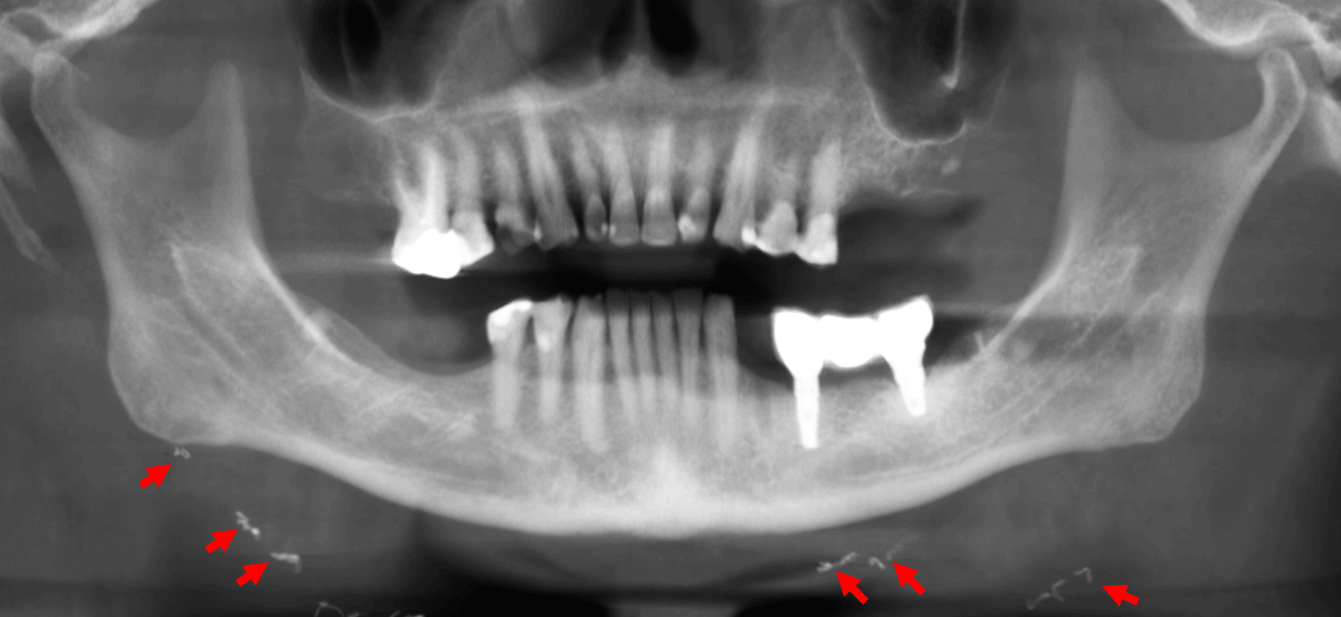

Fig.1

En el estudio con tomografía para implantes dentales, se realizó la reconstrucción panorámica de ambos maxilares (Fig.1) en la cual se observan imágenes hiperdensas en la región submandibular (flechas rojas). Además, se observan múltiples ausencias dentarias y múltiples restauraciones dentarias en el maxilar superior e inferior, y también implantes dentales con prótesis sobre implantes en el tercer cuadrante.